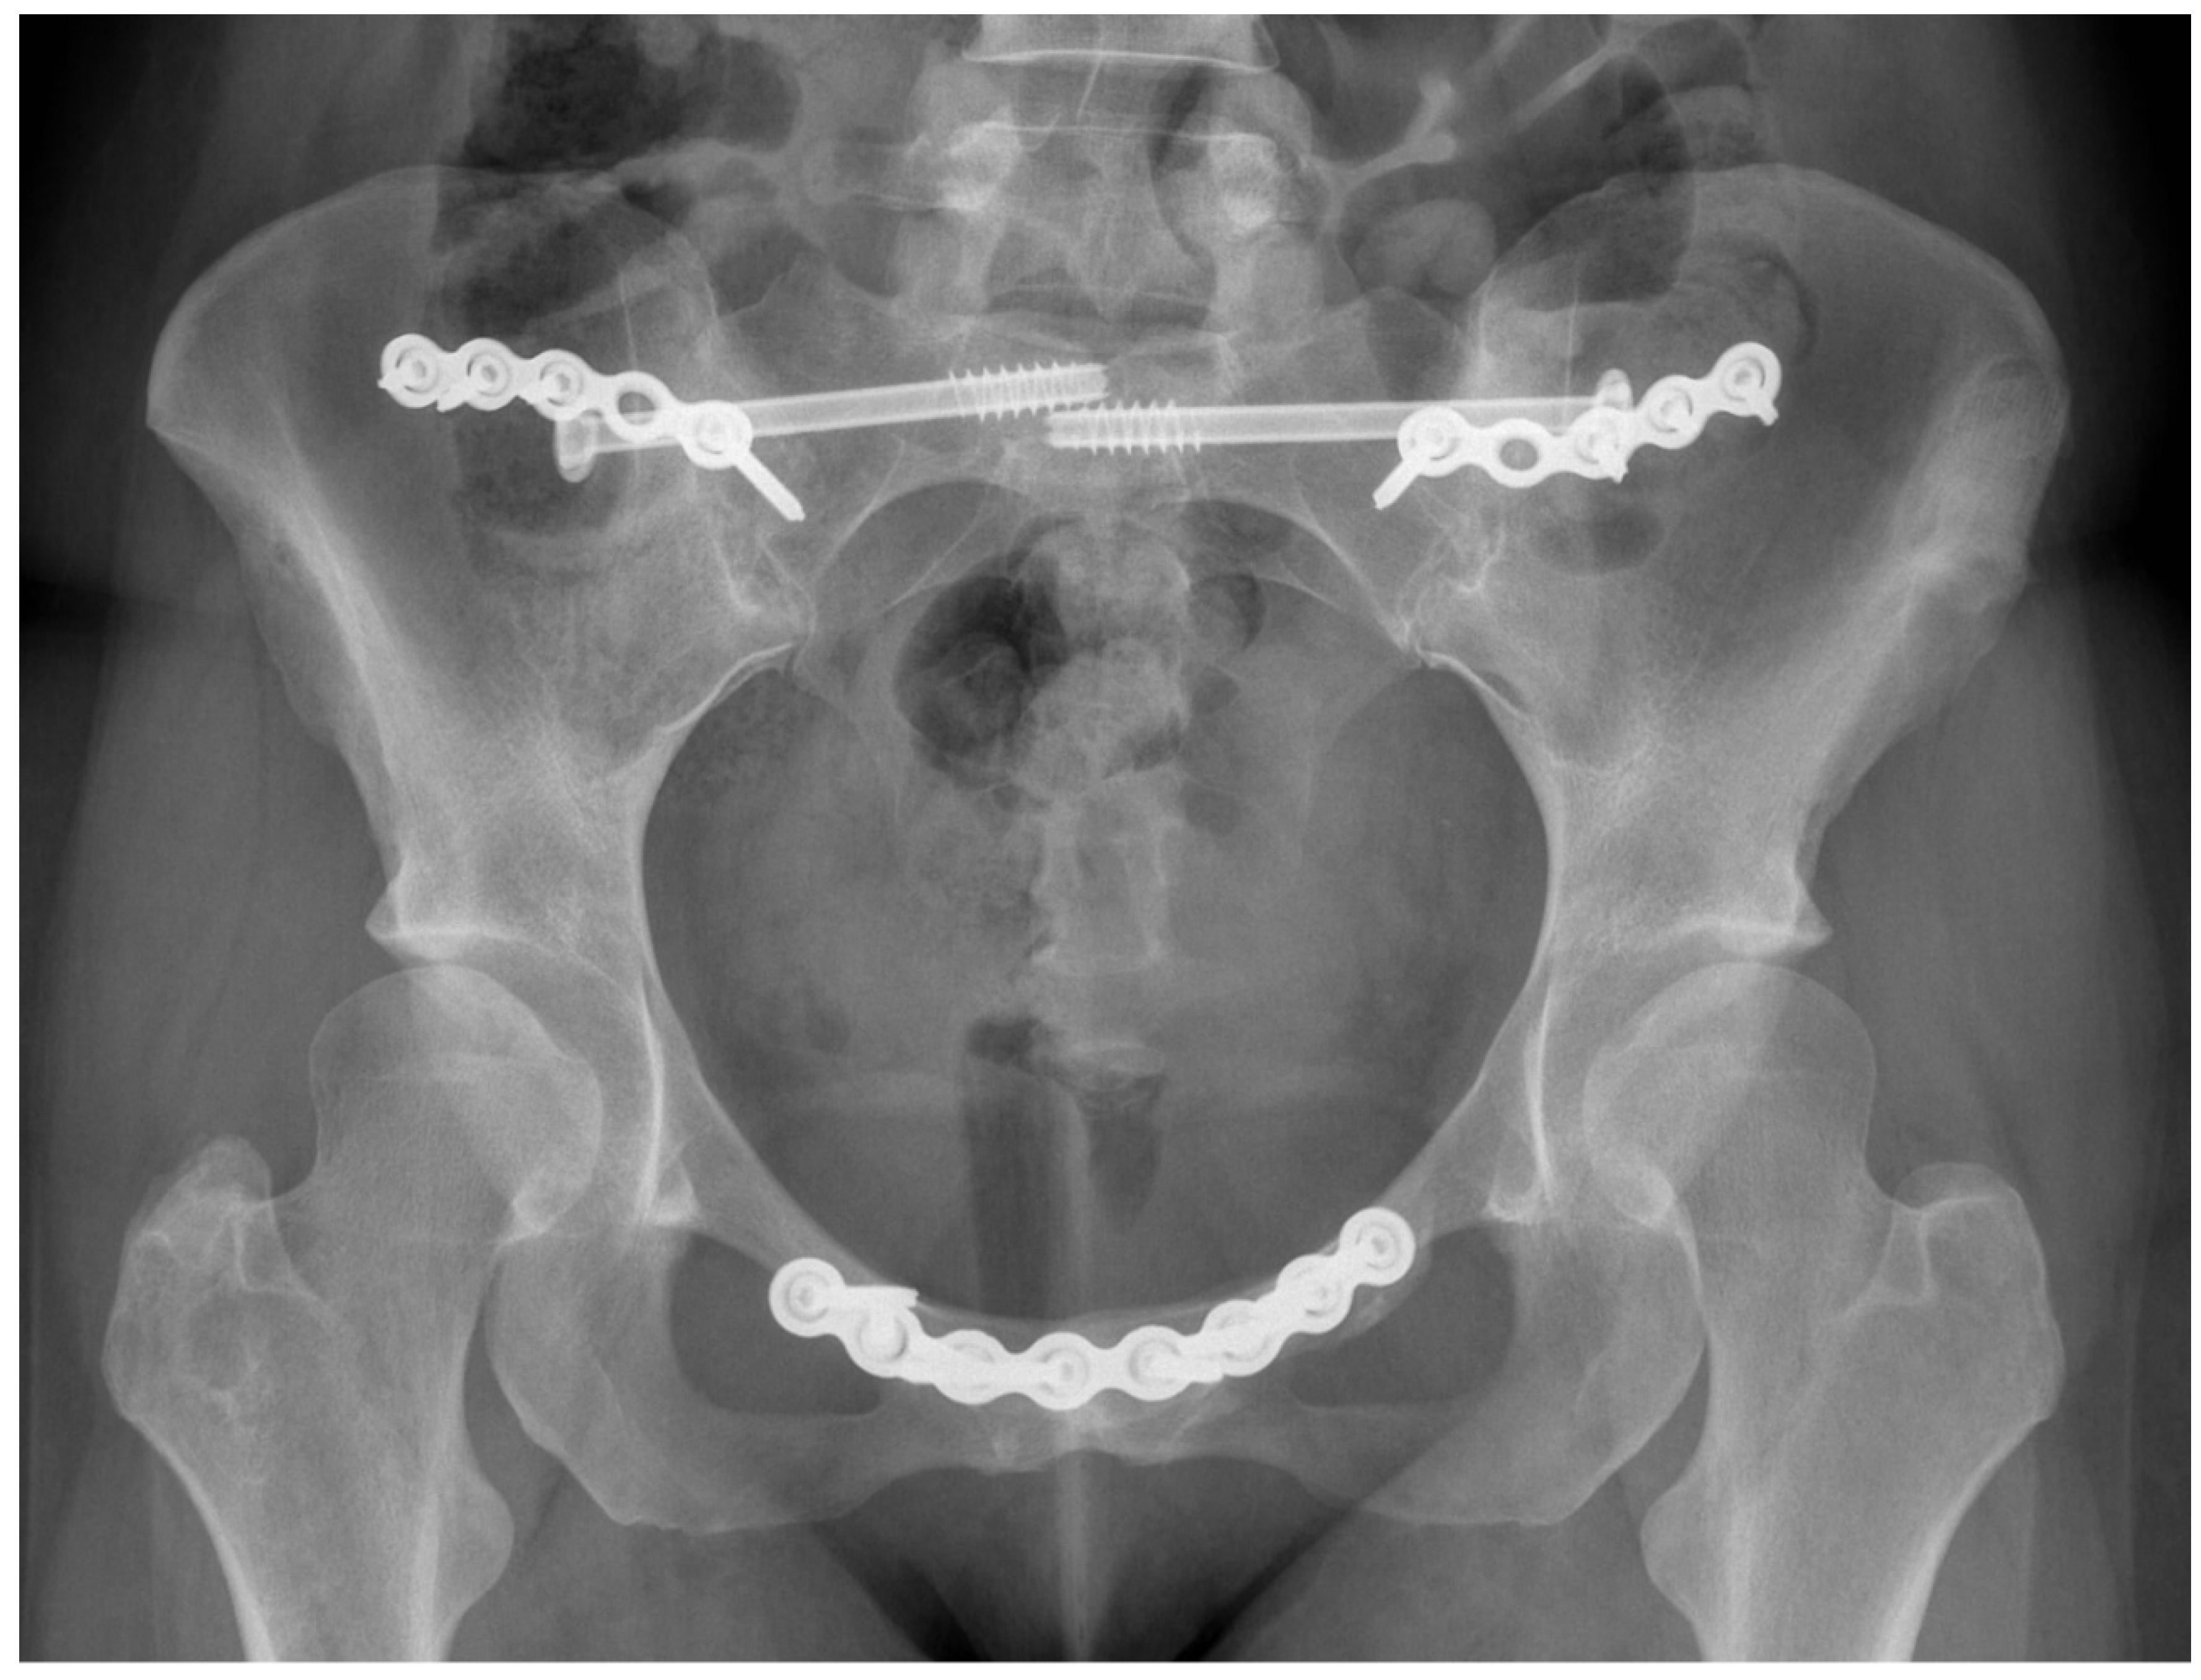

- Van Zwienen, C.M.; Van den Bosch, E.W.; Snijders, C.J.; Van Vugt, A.B. Triple pelvic ring fixation in patients with severe pregnancy-related low back and pelvic pain. Spine 2004, 29, 478–484. [Google Scholar] [CrossRef] [PubMed]

- Kibsgård, T.J.; Røise, O.; Sudmann, E.; Stuge, B. Pelvic joint fusions in patients with chronic pelvic girdle pain: A 23-year follow-up. Eur. Spine J. 2013, 22, 871–877. [Google Scholar] [CrossRef] [PubMed][Green Version]

- Kibsgård, T.J.; Røise, O.; Stuge, B. Pelvic joint fusion in patients with severe pelvic girdle pain—A prospective single-subject research design study. BMC Musculoskelet. Disord. 2014, 15, 85. [Google Scholar] [CrossRef] [PubMed]

- Giannoudis, P.V.; Kanakaris, N.K. Pubic Symphysis Fusion. In Practical Procedures in Elective Orthopaedic Surgery: Pelvis and Lower Extremity; Giannoudis, P.V., Ed.; Springer: London, UK, 2012; pp. 23–28. [Google Scholar]